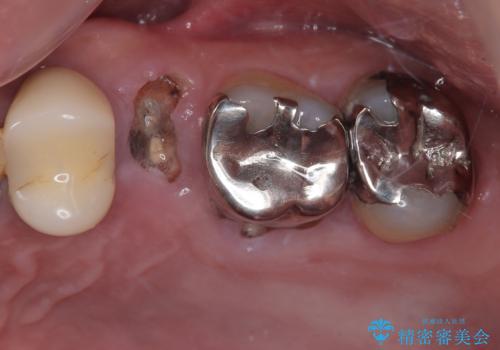

銀歯の下の虫歯|オールセラミッククラウン

担当医 河野豊嘉